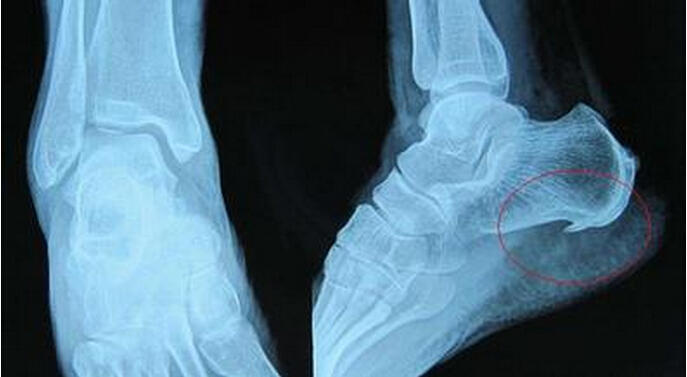

增生性骨关节病是指由于关节退行性变,以致关节软骨被破坏而引起的慢性关节病。又称退化性关节炎、骨关节炎及肥大性关节炎等。

2.继发性骨关节病是指因某种已知原因,例如外伤、手术或其他明显因素而导致的软骨破坏,或关节结构改变。由于关节面摩擦或压力不平衡等因素,造成关节面的退行性变。

起病缓慢,无全身症状,多为50岁以上的中老年。常为多关节发病,也有单关节发病者。受累关节可有持续性隐痛,活动增加时加重,休息后好转。疼痛常不严重,气压降低时加重,与气候变化有关。

有时可有急性疼痛发作,同时有关节僵硬感,偶尔可发现关节内有磨擦音。久坐后关节僵硬加重,稍活动后好转,有人称之为“休息痛”。后期关节肿胀、增大及运动受限,很少完全强直,一般表现为骨阻滞征。